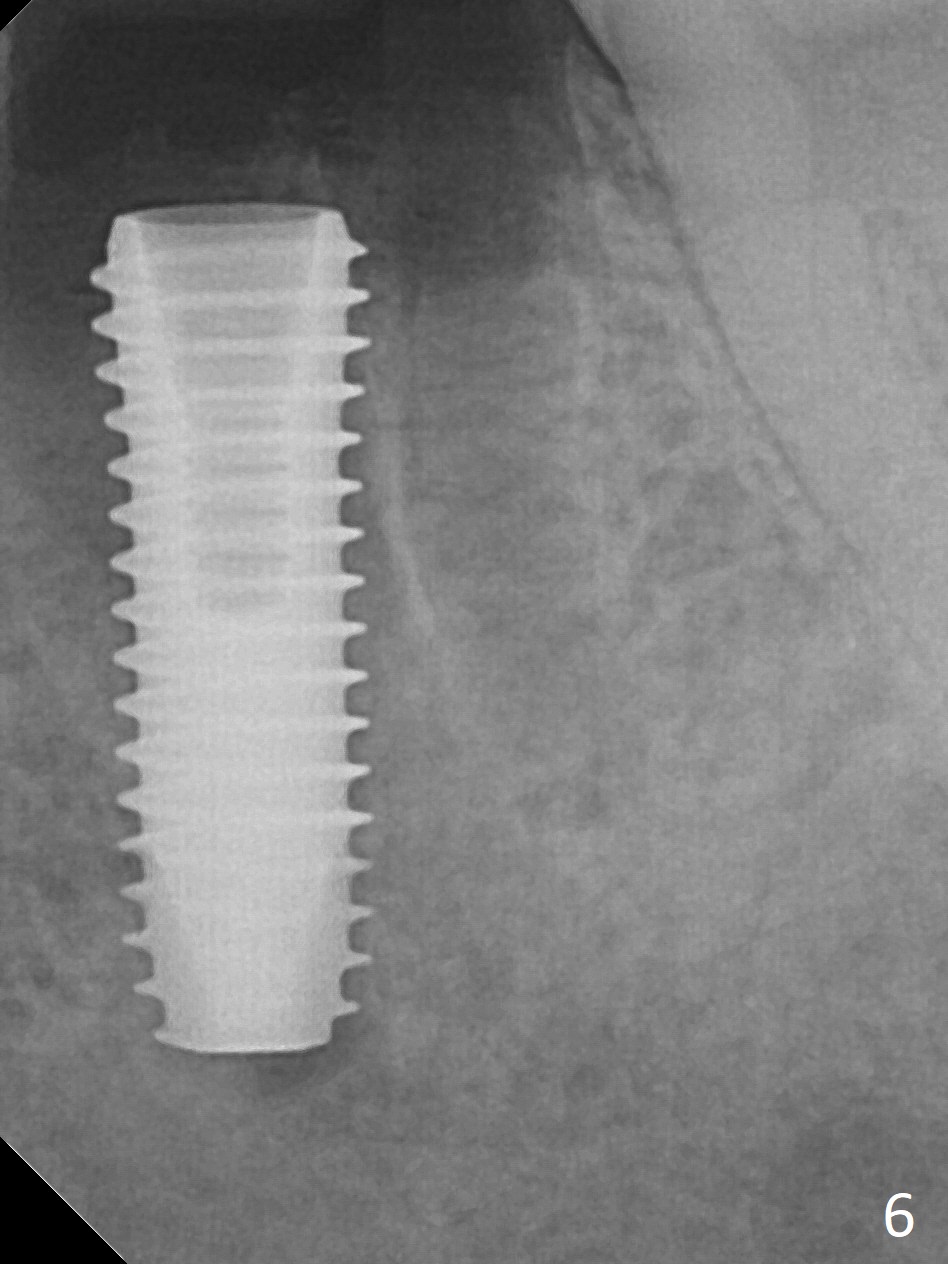

When the patient returns 9 months later, there is severe buccal gingival recession and abscess at #19 (Fig.1 *) with large mesial periradicular radiolucency (Fig.2 *).  The septum is thin and the buccal crest is low after extraction (Fig.3 * (mesial root vertical fracture)).  Osteotomy is initiated in the mesial socket immediately against the septum (Fig.4.5) with ~ 5 mm in the native bone.  Due to severe buccal plate resorption, a shorter implant is placed (Fig.6; 5x15 mm in stead of 18 mm).  There is at least 2 mm gap buccally for Vanilla Graft, which is also placed next to the implant and the neighboring root (Fig.7 *).  There is clearance from the Inferior Alveolar Canal (Fig.8 red dashed line).  Both the mesial and distal sockets heal 5.5 months postop (Fig.9), although the apical portion of the distal socket was not filled with allograft (Fig.7).  The implant was placed mesial.  The straight abutment (6.5x4(4) mm) (Fig.10) is changed to an angled one (5.5 x15 degrees 3 mm cuff (Fig.11)) before impression.  The implant is also placed buccally.  Therefore the implant position is far more important than its length.  The abutment is retightened 2.5 months post cementation, which is related to mesiobuccal placement of the implant (Fig.12).  An ideal trajectory is determined by drawing 2 horizontal lines (at crestal and apical levels: red lines in Fig.13), finding a central point of each line (vertical short line) and joining these 2 central points (Fig.14 pink line).  In fact the ideal osteotomy should have been established distal to the septum in this case.  Guided surgery may alleviate the issue.  The crown is not loose, but the patient feels that the implant tooth cannot sustain mastication.  In fact the screw is removed with hand driver (not wrench).  The abutment hex is rounded and worn.  A new 5.5x4(4) mm abutment is placed (without knowledge of previous use of an angled abutment) with mesial reduction to reduce undercut and buccodistal margin lowered to reduce gingival embrasure. It is that the straight abutment could decrease the chance of screw loosening.  Otherwise the implant has to be removed for better trajectory.